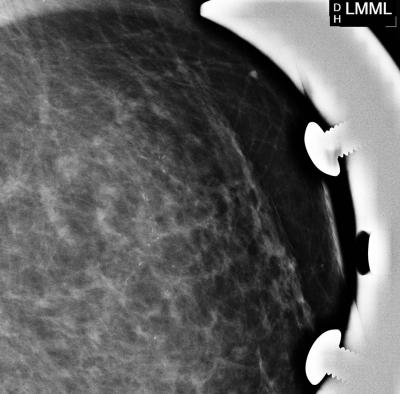

CHICAGO – In a study of screening mammography-detected breast cancers, patients who had more frequent screening mammography had a significantly lower rate of lymph node positivity—or cancer cells in the lymph nodes—as compared to women who went longer intervals between screening mammography exams. Results of the study were presented today at the annual meeting of the Radiological Society of North America (RSNA).

In its earliest stages, breast cancer is confined to the breast and can be treated by surgically removing the cancer cells. As the disease progresses, breast cancer cells may spread to the lymph nodes and then to other areas of the body.

"On its pathway to other places in the body, the first place breast cancer typically drains into before metastasizing is the lymph nodes," said Lilian Wang, M.D., assistant professor of radiology at Northwestern University/Feinberg School of Medicine in Chicago, Ill. "When breast cancer has spread into the lymph nodes, the patient is often treated both locally and systemically, with either hormone therapy, chemotherapy, trastuzumab or some combination of these therapies."

The retrospective study, conducted at Northwestern Memorial Hospital, included 332 women with breast cancer identified by screening mammography between 2007 and 2010. The women were divided into one of three groups, based on the length of time between their screening mammography exams: less than 1.5 years, 1.5 to three years and more than three years. There were 207, 73 and 52 patients in each category, respectively.

Controlling for age, breast density, high-risk status and a family history of breast cancer, the researchers determined that women in the less than 1.5-year interval group had the lowest lymph node positivity rate at 8.7 percent. The rate of lymph node involvement was significantly higher in the 1.5- to three-year and over three-year interval groups at 20.5 percent and 15.4 percent, respectively.

"Our study shows that screening mammography performed at an interval of less than 1.5 years reduces the rate of lymph node positivity, thereby improving patient prognosis," Dr. Wang said. "We should be following the guidelines of the American Cancer Society and other organizations, recommending that women undergo annual screening mammography beginning at age 40."